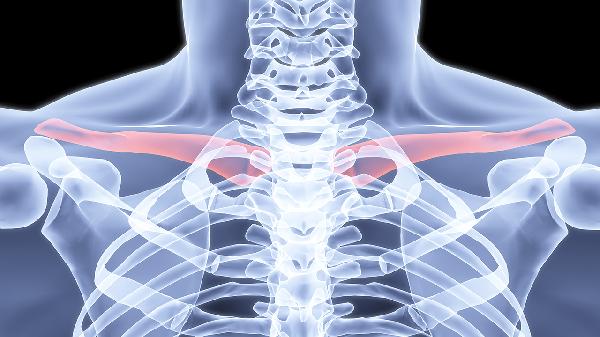

锁骨骨折怎么恢复得快 养治结合恢复骨折锁骨

锁骨骨折可通过保持制动、合理饮食、适度康复训练、药物治疗及定期复查等方式促进恢复。锁骨骨折通常由外伤、骨质疏松、暴力撞击等因素引起,表现为局部肿胀、疼痛及活动受限。